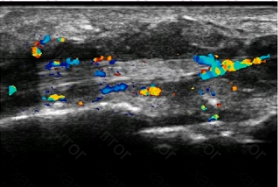

A woman with a history of long-standing rheumatoid arthritis presents with persistent, chronic wrist pain and swelling. What do the patient’s ultrasound images demonstrate?